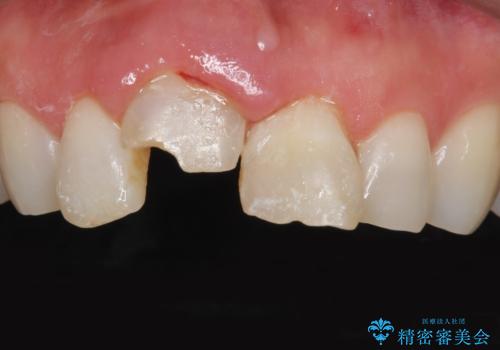

- 転んで前歯が折れたとのことで来院されました。

検査の結果、歯は大きく折れておらず、骨の中に埋め込まれていた状態であったため、部分矯正で歯を引っ張り出していきます。